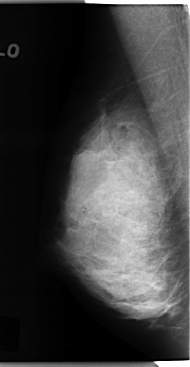

C_0120_1.RIGHT_CC

RIGHT_CC LINES 4720 PIXELS_PER_LINE 2632 BITS_PER_PIXEL 12 RESOLUTION 50 NON_OVERLAY